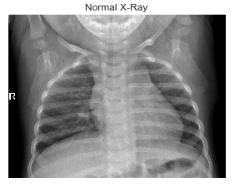

Fig-1:NormalCXRImages Fig-2:PneumoniaAffectedCXRImages